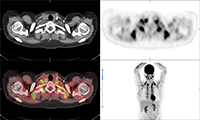

30 year-old woman with history of lymphoma. Axial CT, PET, PET-CT fused, and PET MIP images demonstrate intense FDG activity in the bilateral neck and paravertebral regions with a symmetrical distribution. Cross-sectional images clearly show that activity in the neck corresponds to fat and therefore consistent with brown fat activity. Brown fat activity is seen more commonly in younger patients and is also increased in response to hypothermia (so keep patients warm both pre and post injection of FDG). |